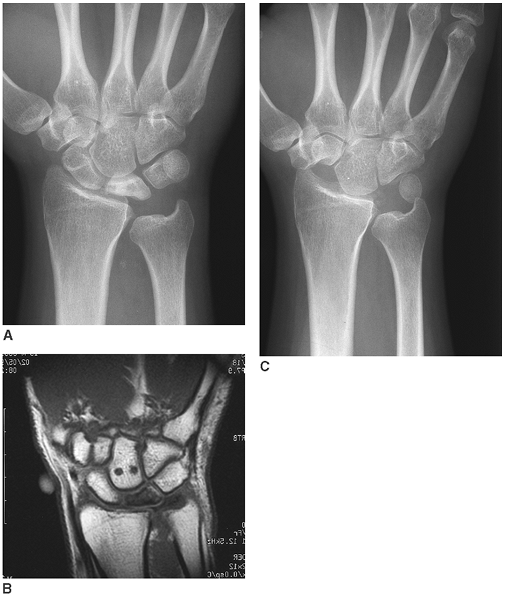

Figure 20-3. A and B: Loss of normal space between the metacarpal and trapezium typical of basilar joint thumb arthritis. C:

After trapezial resection and stabilization of the first to second

metacarpal, a new space for thumb carpometacarpal motion has been

“created.”

Figure 20-4. A: Posteroanterior (PA) wrist radiograph showing “collapse” of the lunate. B:

Magnetic resonance imaging study of the same wrist from the same point

in time showing essentially no vascular signal within the lunate

marrow. C: PA wrist radiograph showing the capitate “seated” in the lunate fossae after excision of the lunate.